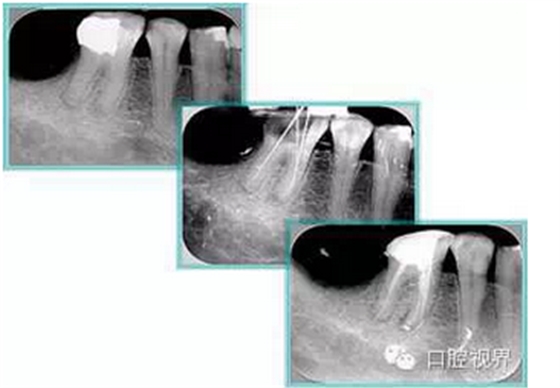

7. 工作長度( WL )再確認

根管初步預備完畢后用 H 銼提拉,之后進行工作長度再確認。插上牙膠尖,拍攝 X 線片,觀察主牙膠尖位置。

3. 主牙膠尖的插入

主牙膠尖應提拉插入,以避免超填。

主牙膠尖常選擇 02 錐度主牙膠尖,有下面幾個優(yōu)點: ( 1 )能夠很好地到達根尖狹窄部。 ( 2 )側方加壓時有較大空間,封閉型好。

4. 輔牙膠尖的插入

主牙膠尖插后選擇側方加壓器進行側方加壓根管充填。

( 1 )側方加壓器的選擇:術前應選擇好,直徑為到達距根尖狹窄部2 -3mm 位置,避免將主牙膠尖擠壓出根尖狹窄部。

( 2 )操作:加壓時沖牙膠位置擠壓,拿出側方加壓器后立即插入輔牙膠尖。

金屬器械取出時牙膠尖有回彈,如果輔牙膠尖放置時間過長,不能到達側方加壓位置,可能造成中間空隙??稍谘滥z尖上蘸一些糊劑送入。關鍵是迅速插入輔牙膠尖。

5. 致密加壓

插入輔牙膠尖后,去除多余牙膠,使用垂直加壓器垂直致密加壓。

操作:進行完根管充填、牙膠放好后,使用垂直加壓器,從根管口向根管方向垂直加壓,壓入 1-2mm 。